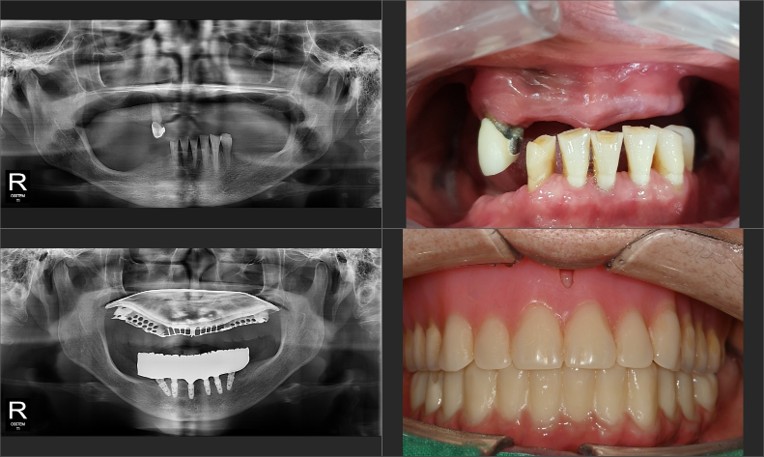

위·아래 모두 틀니를 사용하시던 이번 환자분은 특히 아래쪽 틀니의 들뜸과 통증을 호소하셨습니다.

이번 사례에서는 '올온식스' 공법을 적용했습니다.

• 핵심 원리: 가장 튼튼한 뼈 위치에 6개의 임플란트 기둥을 전략적으로 식립합니다.

• 브릿지 결합: 심어진 6개의 기둥 위에 하나의 일체형 전체 보철물을 연결하여 전체 치열을 회복합니다.

• 장점: 식립 개수가 적어 비용 부담은 줄이면서도, 저작력(씹는 힘)은 자연치아의 80% 이상까지 끌어올릴 수 있습니다.

이번 환자분도 어금니 쪽 뼈가 부족하고 신경선이 가까워 일반적인 수직 식립이 어려운 상태였습니다.

저희 하루임플치과에서는 전방부의 단단한 기저골을 활용해 임플란트를 일부러 기울여 심는 ‘각도 조절 설계’를 적용했습니다.

이는 집도의의 풍부한 임상 경험이 뒷받침되어야 하는 고난도 기법으로

별도의 대규모 뼈이식 없이도 당일 임플란트 식립을 가능하게 합니다.